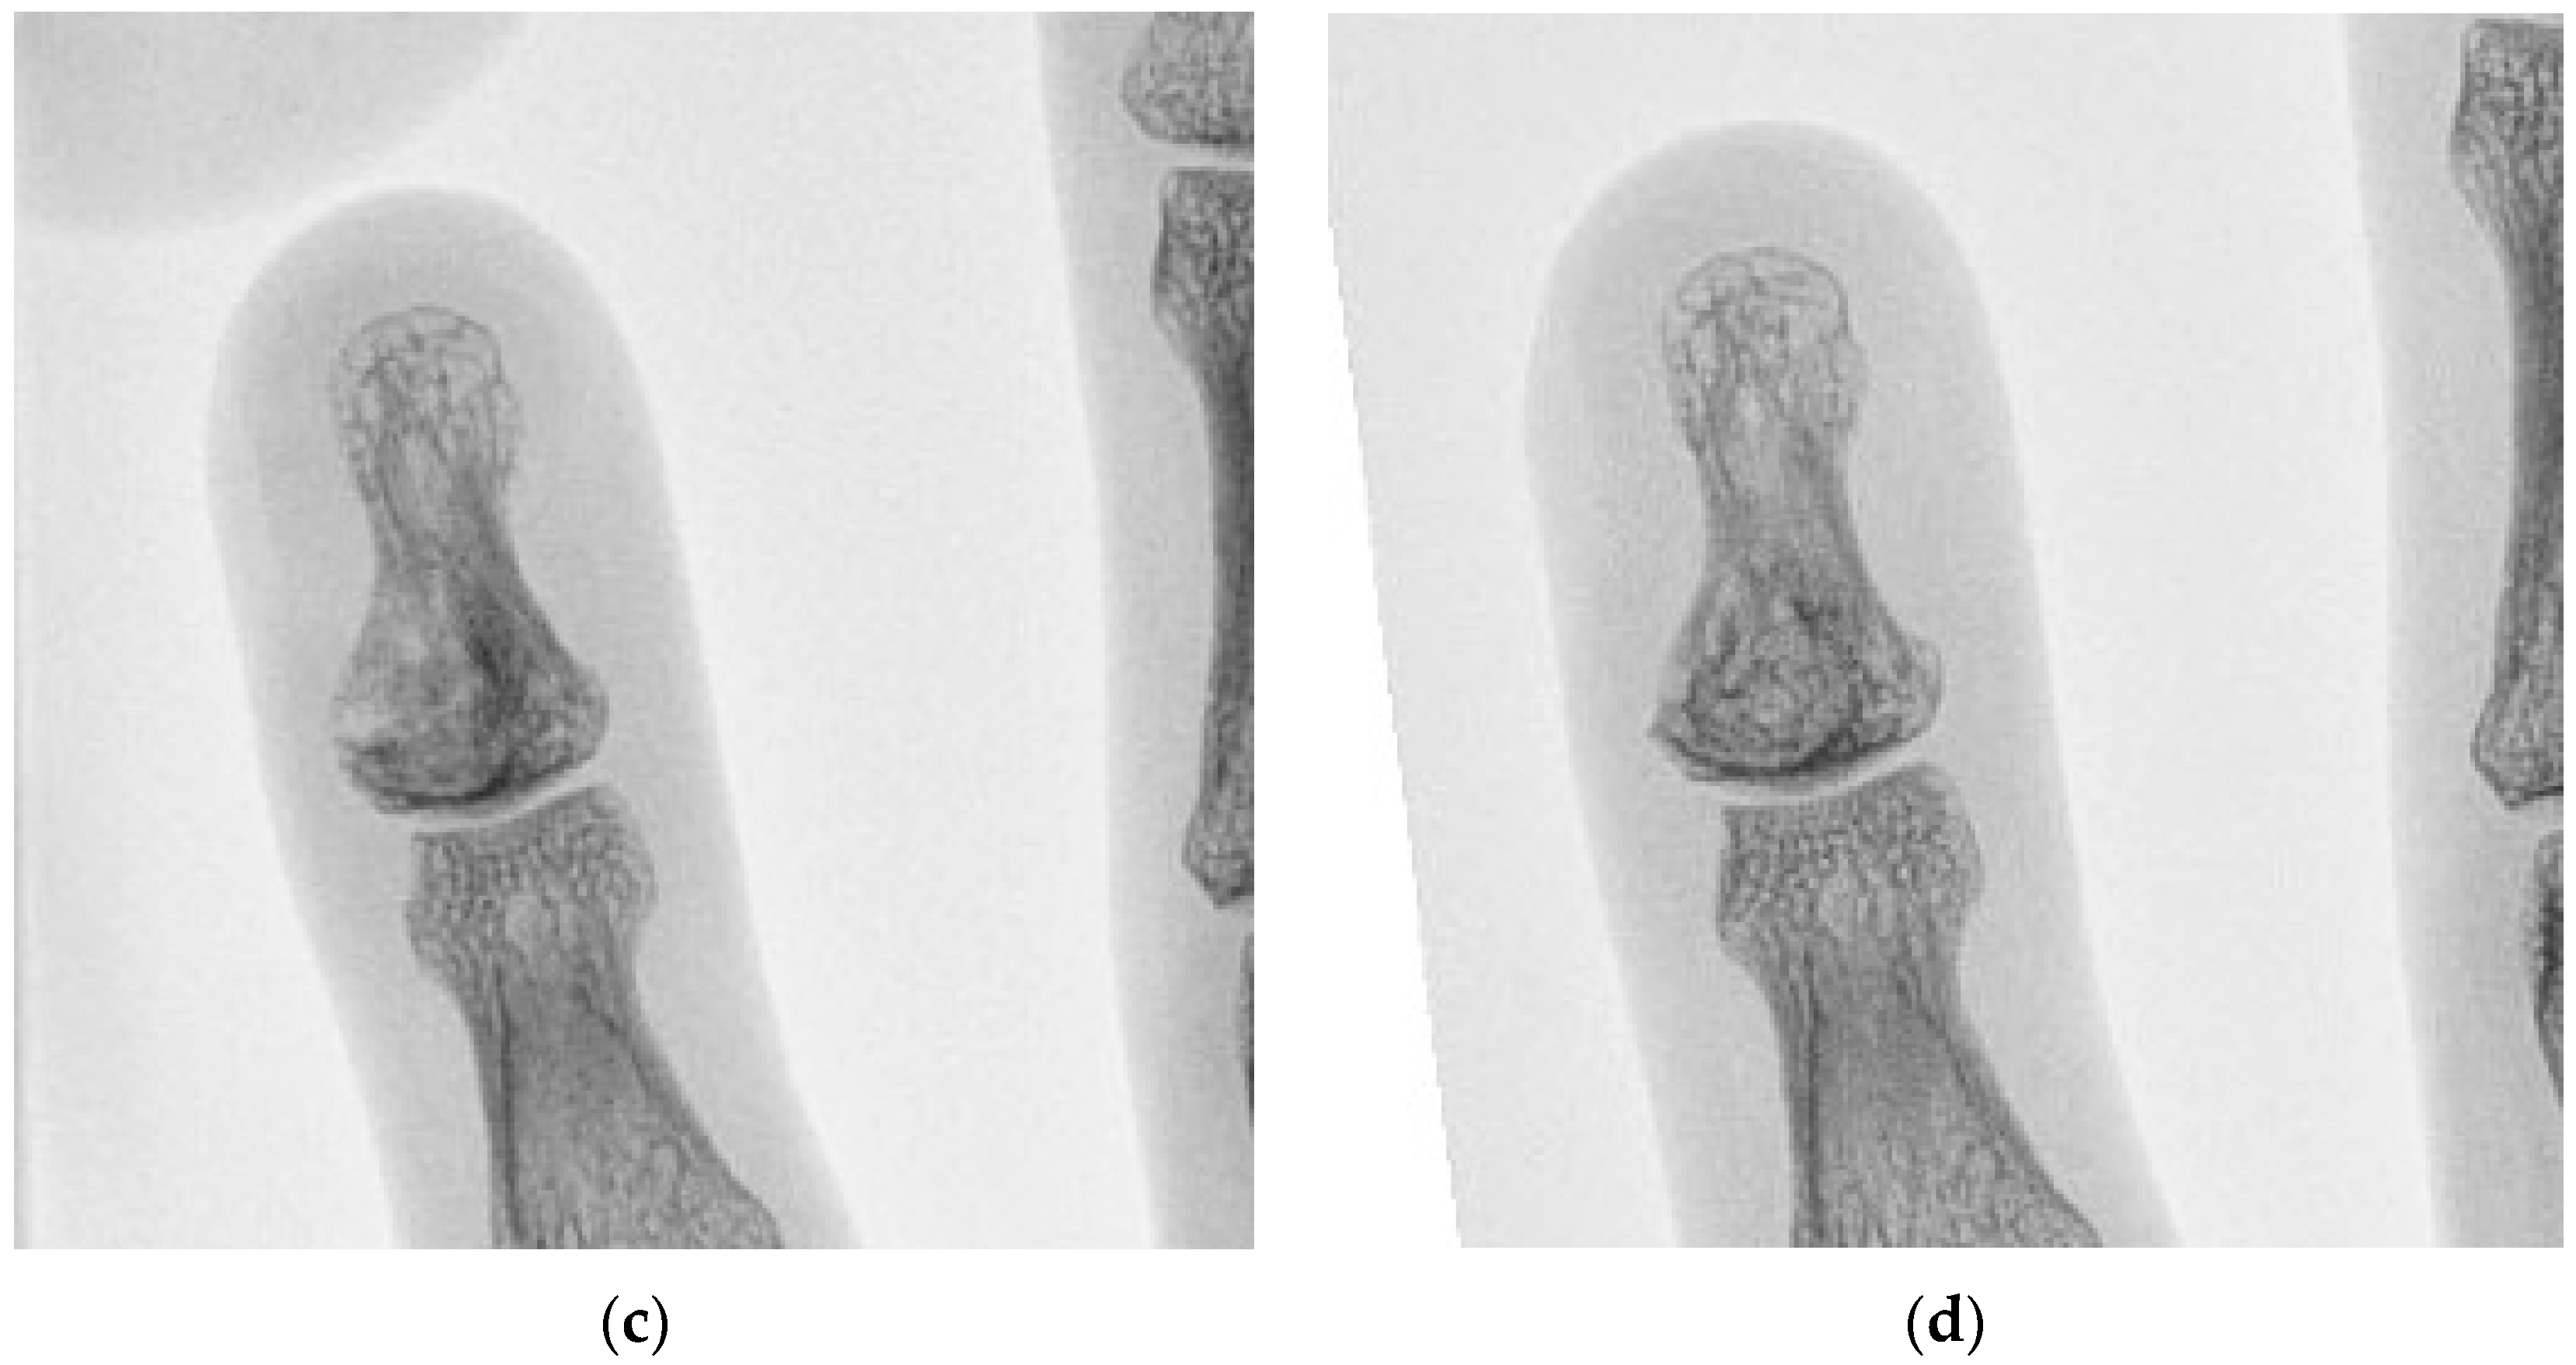

| 2 | 34 M | 1 | Left middle finger P1 | 32 | Enchondroma | 24 |

| 5 | 36 M | 1 | Left little finger P3 | 10 | Enchondroma | 25 |

| 7 | 71 M | 2 | Right middle finger P3 | 20 | Epidermoid cyst | 27 |